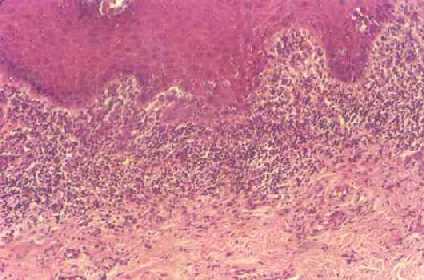

¿Que es el Liquen Plano?

El liquen plano es una enfermedad poco común que causa erupción o lesión inflamatoria y picazón recurrentes en la piel o en la boca. No se conoce la causa exacta de esta enfermedad, pero es probable que esté...